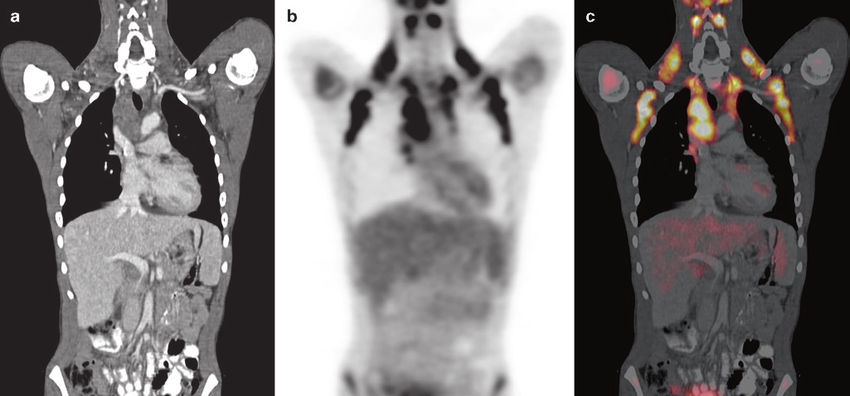

갈색지방은 태생기에 주로 많으며 출생 후 10년 이내에 소실된다. 하지만 퇴화한 줄 알았던 갈색지방을 2009년에 미국 조슐린 연구소와 유럽 및 일본의 연구팀들이 양전자 방출 컴퓨터 단층촬영기(PET-CT)로 발견했다. 확인된 갈색지방 위치는 쇄골ㆍ척추ㆍ목뒤ㆍ어깨 등이었다. 성인 근육 1g=13kcal를 소비하는 반면, 갈색 지방 1g=6,000kcal를 소비한다는 것을 알게 되었다. 이것은 근육에 비해 무려 460배나 에너지 소비 효율이 높다.

양전자 방출 컴퓨터 단층촬영기(PET-CT)에 촬영된 몸속 갈색지방[이미지 출처: 구글]

미토콘드리아와 함께_갈색지방.png 양전자 방출 컴퓨터 단층촬영기(PET-CT)에 촬영된 몸속 갈색지방[이미지 출처: 구글]